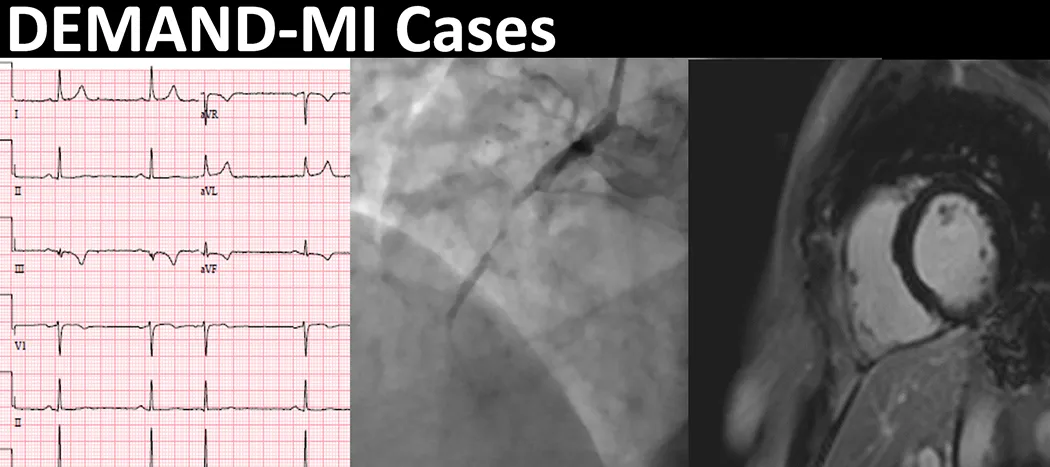

The DEMAND-MI Cases educational resource, launched today & is accessible for free. Image This cardiac imaging educational resource is derived from the cardiac imaging study: "Determining the mechanism of myocardial injury & role of coronary disease in type 2 myocardial infarction" (DEMAND-MI-NCT03338504). The DEMAND-MI educational resource will compile one hundred (100) clinical vignettes for all study participants including history, examination findings, routine hospital investigations such as haematology, biochemistry blood tests, electrocardiogram & study imaging. This educational resource will include: A series of 100 cases with a clinical diagnosis of type 2 myocardial infarction All relevant clinical information on admission Relevant coronary imaging (invasive coronary angiogram or CT coronary angiogram) & cardiac magnetic resonance (CMR) imaging studies An interface which allows you to select & enlarge images Case summaries which outline the adjudication panel's approach, once all available information was reviewed. Today's launch aims to pilot the educational resource using five (5) initial cases. We aim to populate the remainder of the educational resource with the full 100 case complement by 31 Aug 2021. We will let those who register now, know, as batches of new cases go live. Read more about the DEMAND-MI Cases & Study here. Relevant links DEMAND-MI study webpage DEMAND-MI Cases educational resource Heart / cardiovascular Coronary artery disease What is a CT scan? What is a MR scan? 05 May 21. ACC Annual Scientific Session & Expo Social media tags & titles The DEMAND-MI Cases educational resource, launched today & is accessible for free. @chapdoc1 @andabularga @MarcDweck @imagingmedsci @HighSTEACS @jdinaus @MDaghem @EdinUniCVS @TheBHF @BHFScotland Publication date 17 May, 2021